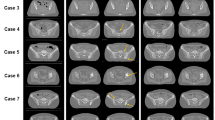

The left column in Fig. 4 shows the results for the attenuation coefficient. N2I can retrieve small structures better using four splits. In the bottom left of the sample (red arrow), a small fiber in the muscle tissue is nearly indistinguishable in the case of two splits but can be seen in the result of four splits. This can also be observed in the bottom right region (blue arrow). The structure in the central muscle region (purple arrow) is also better recovered using four splits. For this reason, it is recommended to use four splits for the application to the attenuation coefficient. This result coincides with the findings of Hendriksen et al.16.

On the contrary, for the electron density, a closer examination of the right column in Fig. 4 reveals that the application with two splits retrieves more details in the muscle structure, which is visible in the left and right fibers (red and blue arrows). Therefore, separating the projections into two splits is preferred for the electron density.

N2I result comparison of two and four splits at \(20\,\hbox {mGy}\). The results of N2I with two (A, B) and four (C, D) splits at \(20\,\hbox {mGy}\) and a high dose reference measurement at \(1231\,\hbox {mGy}\) (E, F). For the electron density, the two splits (B) show more details in the muscle region marked with the red and blue arrow, while four splits (D) have a higher contrast for the small muscle structure in the lipid tissue marked with a yellow arrow. For the attenuation coefficient, the use of four splits (C) reveals more structures in the muscle tissue marked by the red, purple, and blue arrows. The windowing for the attenuation coefficient is: [-3.0, -0.5] x 10-3; for the electron density: [-1.5, 1.5] x 10-2.